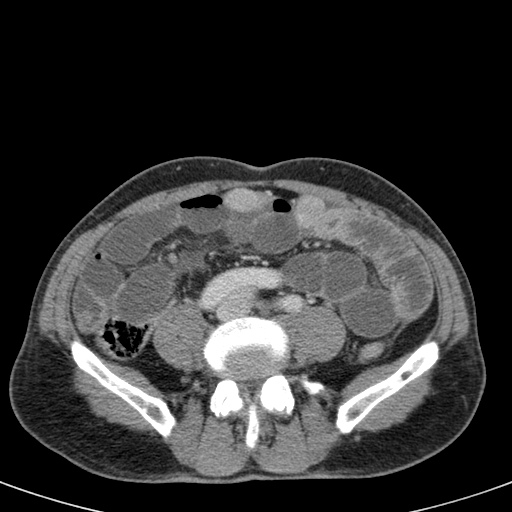

Đây là một bệnh nhân bị tắc ruột non.

Cuộn qua các hình ảnh.

Bạn có thể tìm thấy quai kín và nguyên nhân gây ra nó không?

Khi tiếp nhận bệnh nhân tại phòng cấp cứu với biểu hiện nghi ngờ tắc ruột non (SBO), điều quan trọng nhất chúng ta cần làm, ngoài việc chẩn đoán xác định, là xác định sự hiện diện hay vắng mặt của tình trạng thắt nghẹt.

CT là phương pháp chẩn đoán hình ảnh được lựa chọn trong đánh giá bệnh nhân nghi ngờ tắc ruột non.

Hình ảnh CT của tắc ruột non dạng quai kín phụ thuộc vào hai yếu tố:

- chiều dài đoạn ruột tạo thành quai kín

- hướng của quai ruột so với mặt phẳng tạo ảnh

Nếu quai kín ngắn và nằm trong mặt phẳng tạo ảnh, chúng ta sẽ thấy quai ruột hình chữ U hoặc chữ C.